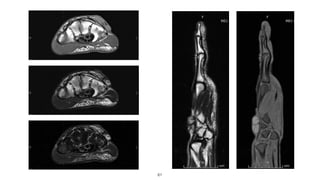

Case #2

47

15-year-old

Mass at thenar area and wrist

Progressive numbness of thumb,

index and middle finger

48

49

50

51

Final Diagnosis:

Lipofibromatous Harmatoma